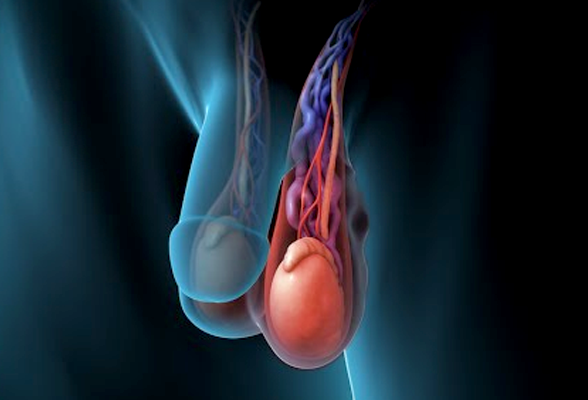

정계정맥류

고환에서 심장쪽으로 흘러야하는 혈류가 고환쪽으로 역류하면서

정맥이 음낭에서 구불구불하게 확장되는 질환입니다.

정계정맥류가 생긴 쪽 고환에 따뜻한 피가 고이고 고환의 온도가 높아지면서 고환 기능 및 생식세포 생성이 저하됩니다.